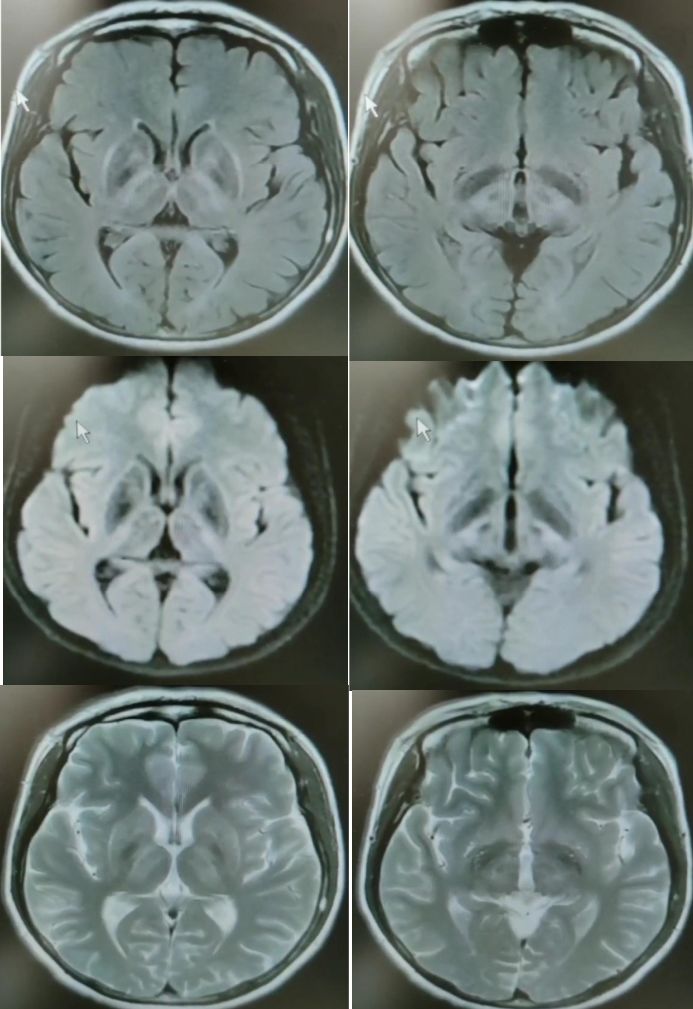

30岁女性,言语不清3年。

答案:肝豆状核变性。又称Wilson’病(WD),是一种常染色体隐性遗传的铜代谢障碍性疾病。主要是由于铜离子异常大量沉积于肝、脑、肾等组织,从而导致全身多系统多器官的损害,以神经系统症状、精神症状、眼部损害、肝脏损害等为主。神经系统最突出的症状是锥体外系症状,包括震颤、构音障碍、肌张力障碍、手足徐动症、共济失调等。构音障碍表现为声音低沉、含糊或嘶哑、缓慢或断续,严重时发不出声,是舌、唇、咽、喉和下颌肌肌张力增高所致。而肝脏的表现通常为肝功能损害、肝硬化、门脉高压症等,一般年轻患者居多。MRI表现为壳核、尾状核头和苍白球在T2WI上呈低信号,齿状核和红核亦可见T2WI为低信号。还可有不同程度的脑萎缩,如两侧壳核对称性裂隙,豆状核、尾状核、大脑皮质、脑干和小脑的萎缩。大小熊猫征为Wilson病的典型特征。